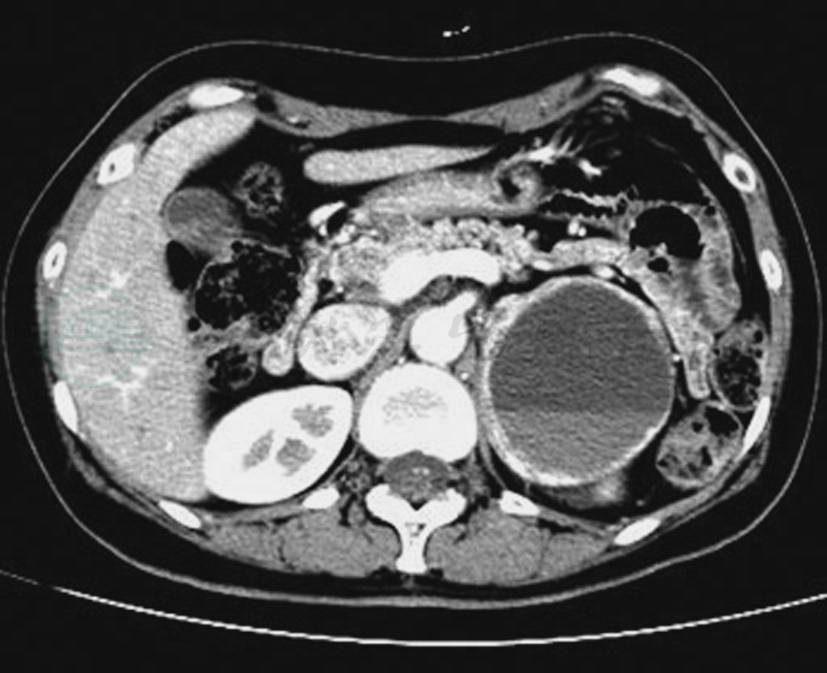

图6左侧肾上腺恶性嗜铬细胞瘤

CT静脉期示左侧肾上腺瘤体,形态不规则,囊变坏死明显,瘤体侵犯肾脏、脾脏及膈肌脚等周围结构